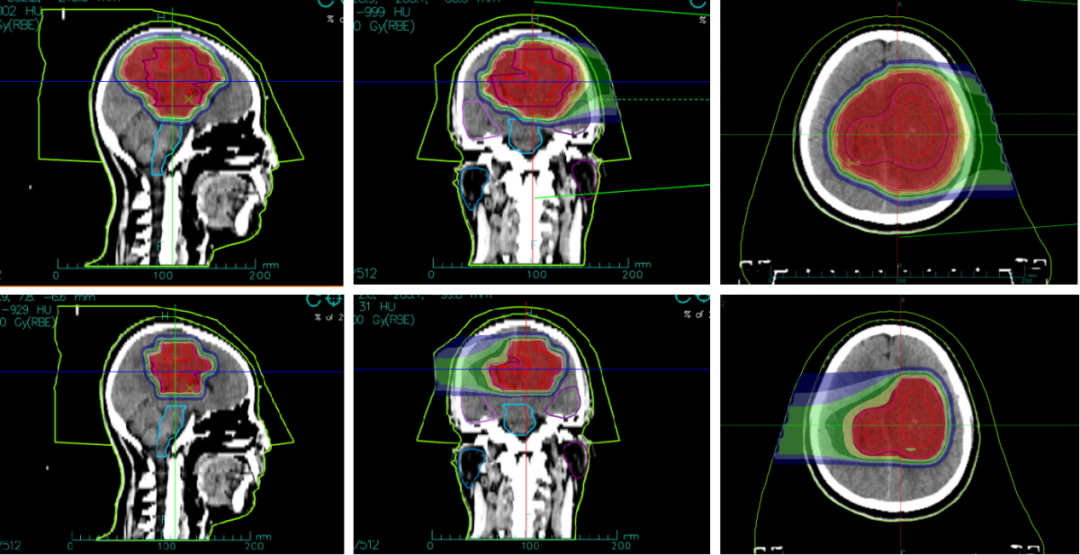

2019年,42岁的杨女士不幸被脑胶质瘤“击中”,犹如晴天霹雳一般,辗转多家医院后在天坛医院确诊为脑胶质瘤,因位置特殊,无法进行手术切除。得知这个消息后杨女士心情低落,寻求最佳治疗方法。2020年5月,杨女士多次出现癫痫,复查后得知肿瘤较前增大,脱水、抗癫痫治疗后症状仍不能缓解。不能做手术,肿瘤长在脑袋里面就像一个定时炸弹,杨女士和家人每天提心吊胆,多番上网查询相关资料,周围的亲戚朋友也在多方打听脑胶质瘤最先进的治疗办法,终于他们看见了有关武威重离子中心的报道,咨询后可以进行重离子治疗,这让杨女士瞬间燃起了生命的希望!2020年6月,杨女士毅然决然的来到我中心,在我中心多学科联合会诊后进行了20次碳离子治疗,治疗期间无任何不适,且未发生过癫痫,治疗结束后肢体无力症状完全缓解,病灶也较前明显缩小。杨女士非常高兴地将每次随访的资料邮寄我科,今天我们收到了治疗结束后30个月的随访资料,病灶已经完全消失,无任何不适,我们真替她感到高兴!

以下是杨女士碳离子治疗近30个月的影像随访资料(图1,图2)

图1 碳离子治疗剂量图